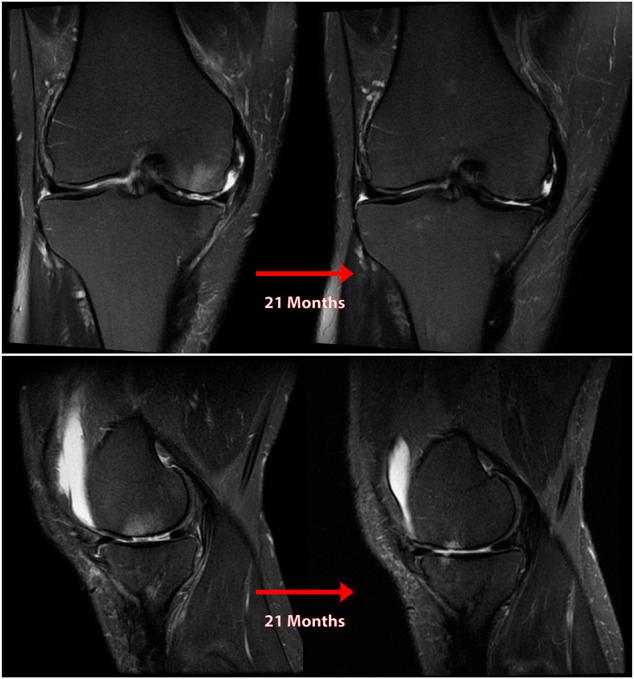

Posterior medial meniscus root tears (PMMRTs) make up a relatively notable proportion of all meniscus pathology and have been definitively linked to the progression of osteoarthritis (OA). While known risk factors for development of OA in the knee include abnormal tibial coronal alignment, obesity and female gender, PMMRTs have emerged in recent years as another significant driver of degenerative disease. These injuries lead to an increase in average contact pressure in the medial compartment, along with increases in peak contact pressure and a decrease in contact area relative to the intact state. Loss of the root attachment impairs the function of the entire meniscus and leads to meniscal extrusion, thus impairing the force-dissipating role of the meniscus. Anatomic meniscus root repairs with a transtibial pullout technique have been shown biomechanically to restore mean and peak contact pressures in the medial compartment. However, nonanatomic root repairs have been reported to be ineffective at restoring joint pressures back to normal. Meniscal extrusion is often a consequence of nonanatomic repair and is correlated with progression of OA. In this study, the authors will describe the biomechanical basis of the natural history of medial meniscal root tears and will support the biomechanical studies with a case series including patients that either underwent non-operative treatment (5 patients) or non-anatomic repair of their medial meniscal root tears (6 patients). Using measurements derived from axial MRI, the authors will detail the distance from native root attachment center of the non-anatomic tunnels and discuss the ongoing symptoms of those patients. Imaging and OA progression among patients who were treated nonoperatively before presentation to the authors will be discussed as well. The case series thus presented will illustrate the natural history of meniscal root tears, the consequences of non-anatomic repair, and the findings of symptomatic meniscal extrusion associated with a non-anatomic repair position of the meniscus.

后内侧半月板根部撕裂(PMMRTs)在所有半月板病变中占比较显著,并且已明确与骨关节炎(OA)的进展相关。虽然已知膝关节OA发展的风险因素包括胫骨冠状面排列异常、肥胖和女性性别,但近年来PMMRTs已成为退行性疾病的另一个重要驱动因素。这些损伤导致内侧间室平均接触压力增加,同时峰值接触压力增加,且相对于完整状态接触面积减小。根部附着的丧失会损害整个半月板的功能,并导致半月板挤出,从而损害半月板的力消散作用。经胫骨拉出技术进行的解剖学半月板根部修复在生物力学上已显示可恢复内侧间室的平均和峰值接触压力。然而,据报道非解剖学根部修复在将关节压力恢复到正常水平方面无效。半月板挤出通常是非解剖学修复的结果,并且与OA的进展相关。在本研究中,作者将描述内侧半月板根部撕裂自然病程的生物力学基础,并将通过一个病例系列来支持生物力学研究,该病例系列包括接受非手术治疗的患者(5例)或内侧半月板根部撕裂接受非解剖学修复的患者(6例)。作者将使用从轴向MRI得出的测量值,详细说明非解剖学隧道与天然根部附着中心的距离,并讨论这些患者的持续症状。还将讨论在向作者就诊之前接受非手术治疗的患者的影像学和OA进展情况。因此呈现的病例系列将说明半月板根部撕裂的自然病程、非解剖学修复的后果以及与半月板非解剖学修复位置相关的有症状半月板挤出的发现。